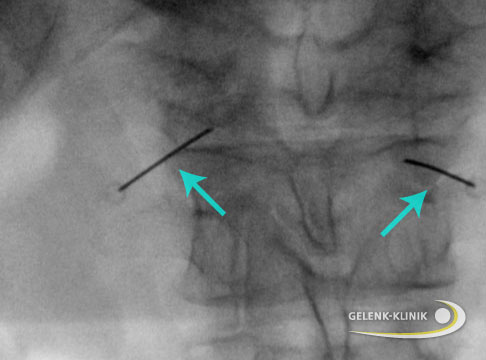

Je nach geplanter Einstichstelle wird der Patient gelagert. Bei einem Sakralblock liegt der Betroffene auf dem Bauch, wird die Wirbelsäule weiter oben infiltriert, sitzt der Patient mit vorgebeugtem Oberkörper. Nach Desinfektion der Einstichstelle führt der Arzt die sehr dünne Hohlnadel ein und schiebt sie unter Röntgenkontrolle bis an die betreffende Stelle vor. Meist wird dann durch die Nadel ein Kontrastmittel injiziert, um im Röntgenbild die korrekte Lage der Nadelspitze zu überprüfen. Danach spritzt der Arzt das Medikament oder - wenn nötig - auch ein Medikamentengemisch.

Infiltration der Iliosakralgelenke (ISG-Block)

Blockaden oder Entzündungen im Kreuzbein-Darmbein-Gelenk (Iliosakralgelenk) kann man ebenfalls mit einer Infiltration lindern. Gespritzt wird ein lokales Betäubungsmittel, evtl. auch als Gemisch mit einem Entzündungshemmer (Kortison), entweder in den betroffenen Gelenkspalt oder in den umgebenden Bandapparat.